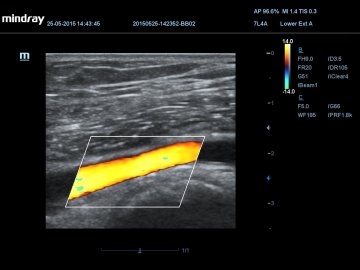

HR-flow™ режим отображения кровотока с высоким временным и пространственным разрешением для точной и однородной визуализации сосудов, в том числе самых мелких